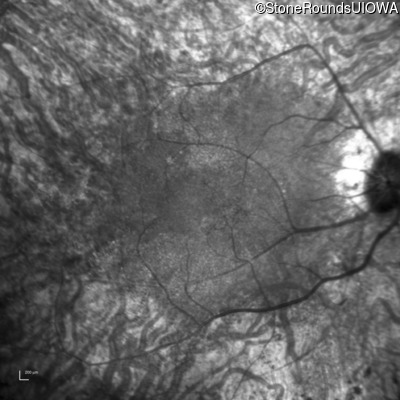

Infrared Fundus Photograph - Right - 20/40 +1

Exemplar